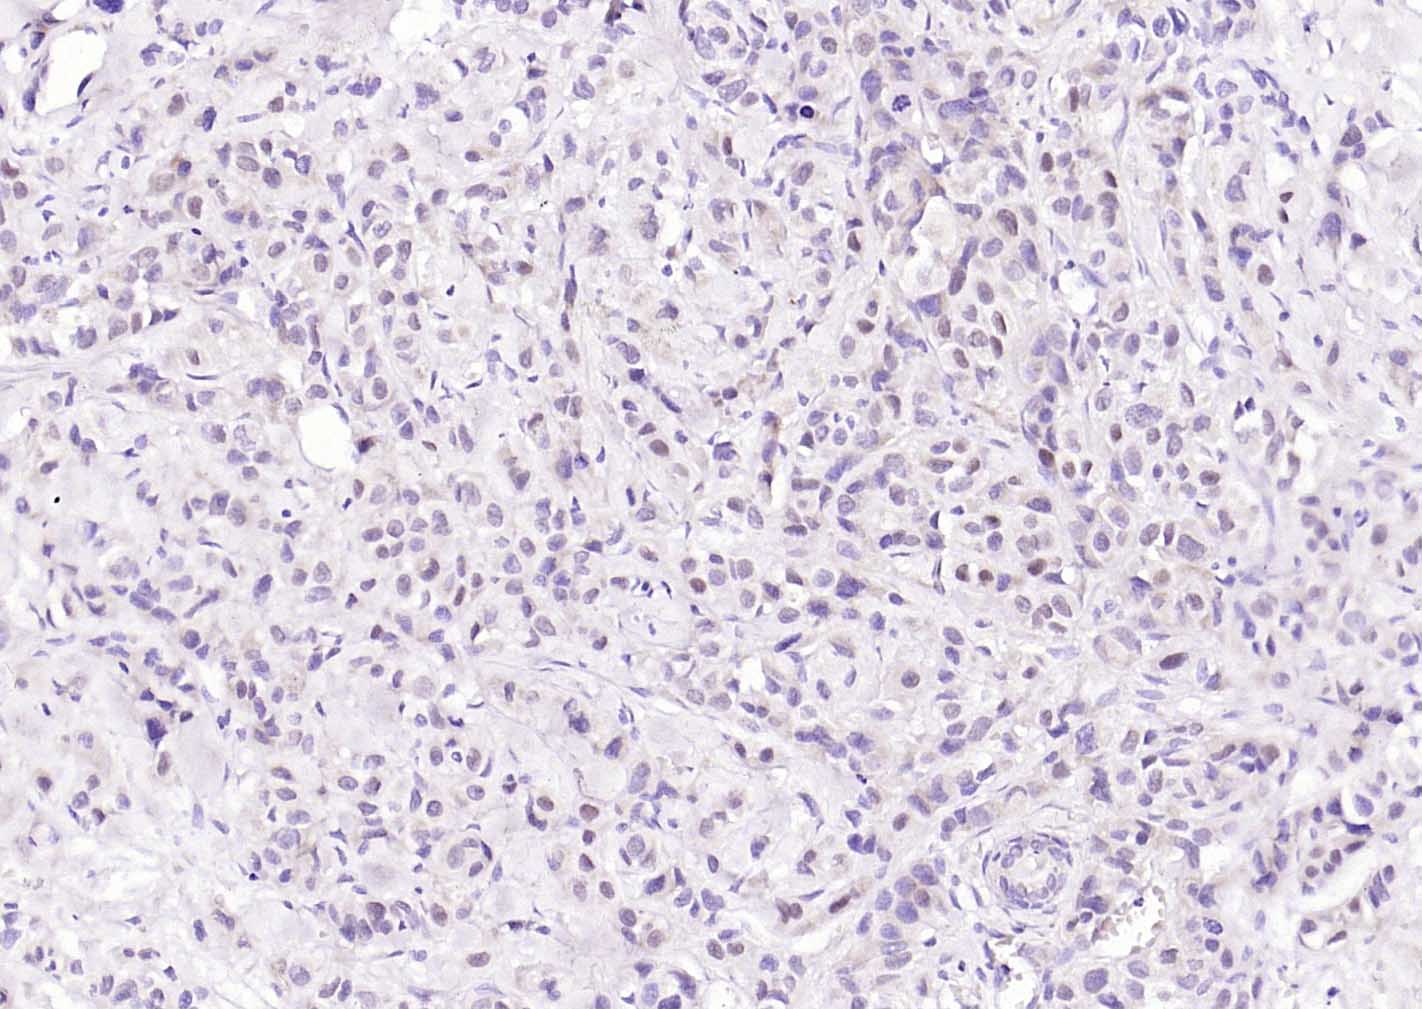

Paraformaldehyde-fixed, paraffin embedded (human endometrium); Antigen retrieval by boiling in sodium citrate buffer (pH6.0) for 15min; Block endogenous peroxidase by 3% hydrogen peroxide for 20 minutes; Blocking buffer (normal goat serum) at 37°C for 30min; Incubation with (Estrogen receptor alpha) Monoclonal Antibody, Unconjugated (bsm-60803R) at 1:300 overnight at 4°C, followed by operating according to SP Kit(Rabbit) (sp-0023) instructionsand DAB staining.

Paraformaldehyde-fixed, paraffin embedded (human breast carcinoma); Antigen retrieval by boiling in sodium citrate buffer (pH6.0) for 15min; Block endogenous peroxidase by 3% hydrogen peroxide for 20 minutes; Blocking buffer (normal goat serum) at 37°C for 30min; Incubation with (Estrogen receptor alpha) Monoclonal Antibody, Unconjugated (bsm-60803R) at 1:300 overnight at 4°C, followed by operating according to SP Kit(Rabbit) (sp-0023) instructionsand DAB staining.